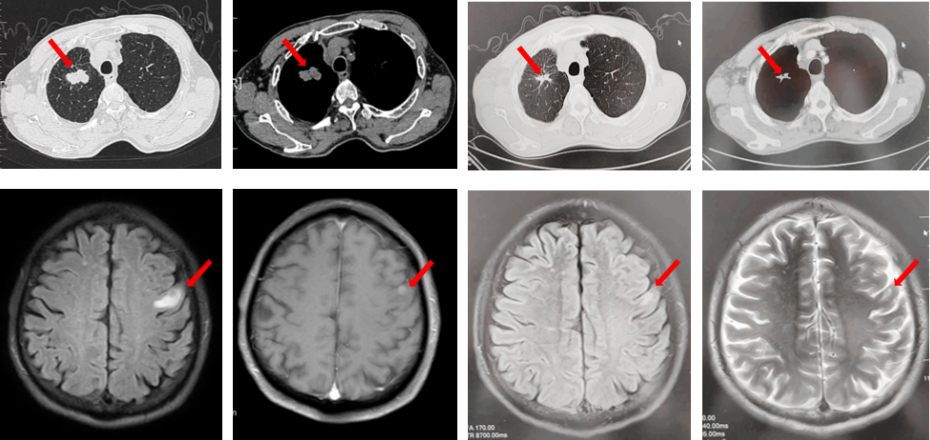

2022年7月至2022年11月行贝伐珠单抗联合培美曲塞/顺铂方案治疗6周期,2周期后评效PR,4周期后评效SD-(如图1)。第6周期治疗结束后患者自行终止治疗。

图1:由左至右分别展示基线(A.)及一线治疗后改变(B.和C.)。红色箭头指示病灶位置,由上至下分别为右肺肿物、右侧胸膜转移病灶及胸腔积液、左侧胸膜转移病灶、多发纵隔淋巴结肿大。

2023年3月患者因咳嗽伴胸闷复查出现全面PD。2023年3月-2023年4月重启原方案贝伐珠单抗联合培美曲塞/顺铂治疗2周期。2023年5月复查评效PD。行左锁骨上淋巴结穿刺,病理回报:左锁骨上见异型细胞,考虑为癌可能性大。组织NGS基因检测:MET基因扩增(变异倍数)2.0倍,TP53错义突变,PD-L1(22C3):TPS 75%。2023年5月-2023年8月改行替雷利珠单抗联合紫杉醇脂质体治疗4周期,2周期后评效SD。(如图2)

图2:A.代表一线治疗停药后病情进展,右肺上叶肿物、右侧胸膜转移灶及纵隔淋巴结较前增大、增多,右侧胸腔积液较前增多;B.原方案重启后复查评效右肺上叶肿物及纵隔淋巴结较前略饱满,右侧胸腔积液较前明显增多;C.更改二线治疗方案后整体病灶较前无显著变化。